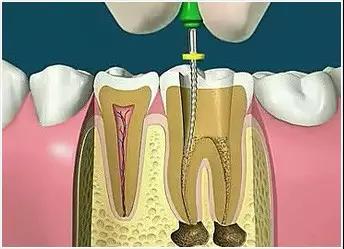

4、根管預備

根管清理成形的目的是去淨根管壁上的感染物,通過根管器械的切削作用去除感染的牙本質並清理根管壁細菌以利於根管充填。

5、根管沖洗、消毒

根管沖洗的目的是清除微生物、沖掉殘渣,潤滑根管器械和溶解有機殘渣。然後,再進行根管消毒,使根管內達到無菌狀態。